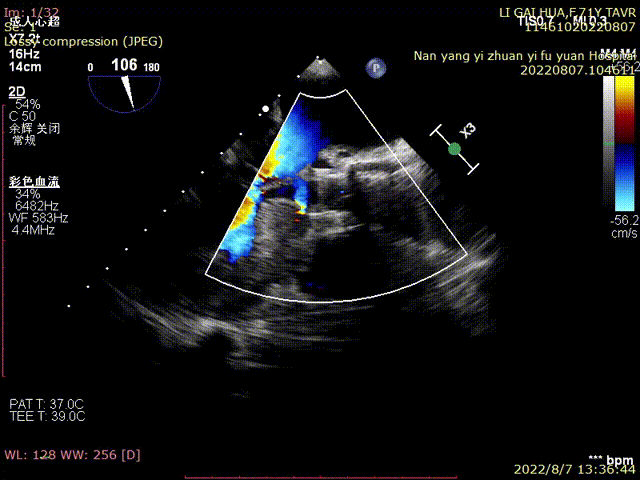

瓣膜释放后超声评估:

术中,心外体外循环科郑军医师全程待命。彩超室张俊鹏老师全程跟台,术后行超声探查未见瓣周漏,血压改善。

术中及术后未出现相关并发症,瓣膜植入位置完美,患者症状得到明显改善,手术圆满完成。

术中20mm球囊预扩可见明显腰征,无瓣周漏,左冠充盈速度可。选择TaurusElite  AV23瓣膜送至主动脉弓,输送系统轻松过弓及跨瓣,精准定位无冠窦最低点,利用可回收功能,术中对位置进行适当调整,大大提升了瓣膜精准释放的几率,保证了手术的安全性。

TaurusElite AV23瓣膜经过2次调整之后,第3次释放定位位置接近瓣环,心脏瓣膜团队精确定位,零位释放,瓣膜在术前评估的位置牢牢锚定!整个手术过程连贯如行云流水,团队配合默契,操作细致熟练,主动脉根部造影及即时食道超声提示无瓣周漏,TaurusElite首秀成功!